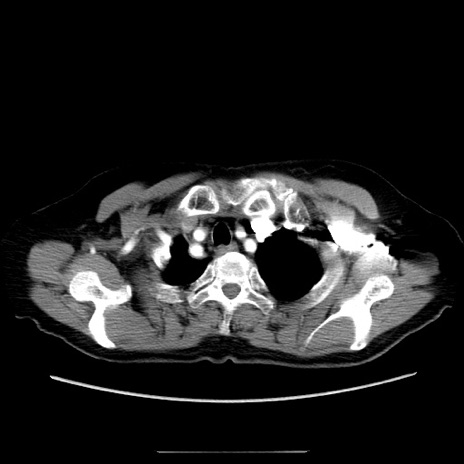

症例5(横断像)

【症例】70歳代女性

【主訴】お腹が張る

【現病歴】1週間くらい前から腹部膨満の自覚あり。昨日夜から増悪したため、本日救急外来受診。

【身体所見】意識清明、BT 36.5℃、BP 165/106mmHg、HR 80bpm、SpO2 98%、腹部:膨満、軟、自発痛・圧痛なし、触診にて不快感あり、腸蠕動音:減弱

【データ】WBC 12600、CRP 1.04